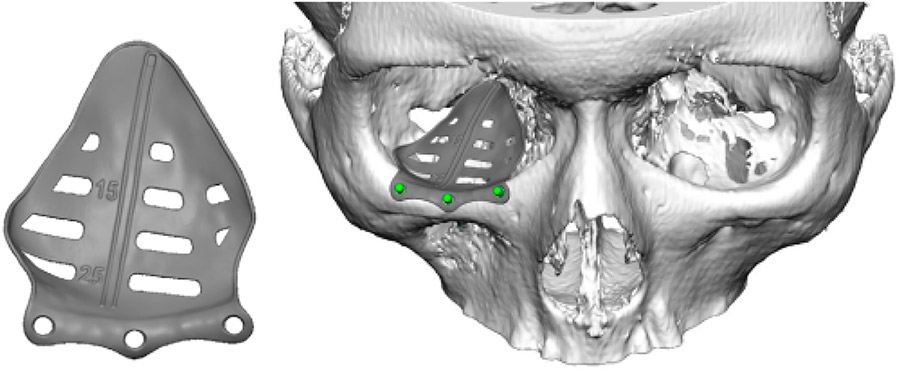

Because of a superior performance over standard implants, patient-specific implants, developed by computer assisted design and computer assisted manufacturing (CAD/CAM) systems, for craniomaxillofacial reconstruction have grown in popularity in the last decade. Customized implants allow a more precise adaptation to the region of implantation, ideal shape and symmetry, with reduced surgical times, and better cosmetic outcomes.

The patient underwent a Caldwell-Luc approach and concurrent orbital floor reconstruction. A one-stage approach was chosen for a faster recovery and single surgery. Correction of enophthalmos and dystopia was performed using a patient-specific CAD/CAM implant (Fig. 3) assisted by intraoperative navigation and CT scan (Fig 4.). The 0.3mm orbital floor titanium plate was placed through a transconjunctival approach (Fig. 5). The patient was found to be complaint free and full recovered at 6th-month follow-up (Fig 1.).

Furthermore, the osseous remodeling and anatomic landmarks loss present in this syndrome imply a huge challenge when trying to reconstruct the orbit with stock implants. In addition, preformed titanium meshes may facilitate the bending process, but it is often difficult to predict the exact positioning of the mesh, lengthens the operative time and does not produce as satisfactory aesthetic and functional results when compared to a specific implant. On the other hand, the use of a customized virtual planned implant, as in our case, enables a precise orbital reconstruction restoring shape and volume accurately with symmetric replacement of the eyeball. Since these implants are specifically designed to fit in a stable and precise position, the risk of damaging the optic nerve and other important structures minimizes.

Moreover, virtual surgical planning can offer the surgeon a better understanding of the anatomy. Intraoperative navigation and CT intraoperative control, add extra safety and greater accuracy to the procedure, controlling ideal positioning of the implant and avoiding complications regarding optic nerve damage. The use of intraoperative navigation has been shown to offer a significantly better orbital volume and eyeball projection, without increasing surgery duration. Customized titanium implants accurately reproduce orbital contours thus restoring orbital volume. This reduces operative time and improves the functional and aesthetic outcomes of post-traumatic orbital reconstruction.